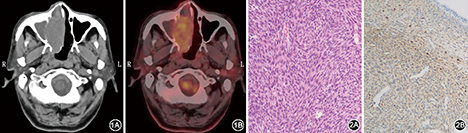

患者男,81岁,因右侧鼻塞1年,加重伴出血2个月余,于2013年8月入院。患者1年前无诱因出现右侧鼻塞,间断发作,受凉后加重,无鼻痒、打喷嚏,未行治疗,渐出现右侧鼻流脓涕,近2个月来,鼻塞加重,持续发作,时有涕中带血,流脓涕及嗅觉减退,无耳闷及头痛等,遂入院治疗。入院后查体:一般情况良好,心肺腹未见明显异常。外鼻无畸形,鼻前庭无肿胀、无压痛,右侧鼻腔见新生物,堵塞至鼻前庭,表面欠光滑,右面部无膨隆,软、硬腭无改变,眼球无移位,活动好,左侧鼻腔未见新生物,鼻窦区无压痛,全身未触及肿大淋巴结。CT扫描可见:右侧鼻腔软组织密度影充满整个鼻腔,密度欠均匀,平均CT值43 Hu,部分鼻窦骨质变薄(图1A)。PET-CT示右侧鼻腔内软组织肿块,FDG代谢弥漫性稍增高,SUV最大值6.40。右上颌窦、筛窦、蝶窦、额窦黏膜增厚,左上颌窦及额窦充气良好,黏膜无增厚(图1B)。初步诊断:右侧鼻腔占位,肿瘤待排除。入院后完善心肺功能检查,未见手术禁忌,遂于入院后第7天在全麻下行鼻内镜下右侧鼻腔肿瘤切除+右侧鼻窦开放术,术中以息肉钳咬除部分鼻腔肿块送快速病理,切吸钻逐步切除肿瘤,见肿瘤蒂部位于鼻中隔后端,术中冰冻病理示:(右侧鼻腔)梭形细胞肿瘤,倾向为低度恶性或恶性。收缩鼻腔黏膜,切除右侧钩突,开放前后筛,见筛窦黏膜水肿伴息肉增生,扩大右侧上颌窦口及额窦口,见窦内有脓液,吸除后检查右侧鼻腔无出血,填塞鼻腔。术后病理:镜下病变组织表面为黏膜,上皮下为束状及片状排列的肿瘤细胞,细胞呈较一致的短梭形,界限不清,胞质较少,核椭圆形,浅染,核仁不明显,核分裂象不易查见(图2)。免疫组化:AE1/AE3(-),EMA(-),CD99(+),Calponin(+),Vimentin(+),Ki-67(约5%+),S-100蛋白(-),SMA(-),MSA(-),CD117(-),CD34(弱+),Desmin(-),bcl-2(-),CD31(-),Caldesmon(-)。病理诊断:右侧鼻腔滑膜肉瘤。术后拟行放疗,因家属考虑患者高龄,拒绝行放疗,门诊鼻内镜随访2年,见鼻腔黏膜光滑,肿瘤未见复发。

鼻腔滑膜肉瘤的临床表现无特异性,可出现类似于慢性鼻-鼻窦炎及鼻息肉的症状,鼻塞、流涕、鼻出血及随肿物增大出现头痛、外鼻畸形、眼球突出或复视、耳闷等邻近器官受累的症状[2],本例患者主诉鼻塞及鼻出血,缺乏特异性。其影像学表现亦无特异性,但影像学检查可明确肿瘤大小及与邻近组织之间的关系。CT表现肿瘤密度与肌肉呈等或略低密度,肿瘤内坏死、囊变区呈更低密度,部分可见斑块状或斑点状钙化,多位于肿块的周边,少数病例可表现为广泛的钙化或骨化[3]。PET/CT具有融合解剖成像和代谢显像特点,对肿瘤原发灶或淋巴结转移等方面具有明显诊断优势,SUV≥2.5者高度提示为恶性肿瘤。本例患者CT见右鼻腔内软组织密度影,密度欠均匀,部分鼻窦骨质变薄。PET-CT示肿块FDG代谢弥漫性稍增高,SUV最大值6.40,符合鼻腔恶性肿瘤的病变特点。鼻腔滑膜肉瘤发病率极低,PET-CT作为肿瘤诊断中的先进技术,对恶性肿瘤的诊断具有重要价值。鼻腔滑膜肉瘤病例较少,需在临床诊疗过程中进一步收集病例,明确PET-CT在该病诊断中的应用价值。